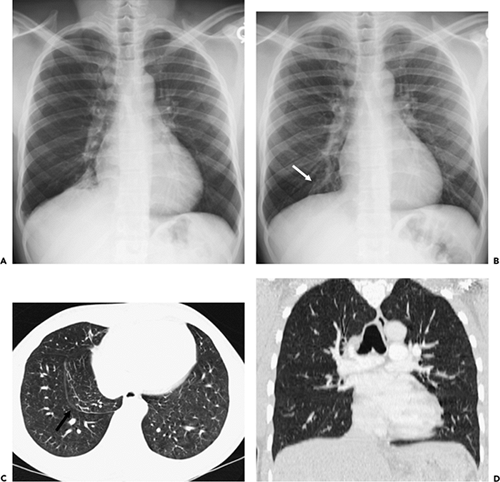

Tap on/off image to show/hide findings. The average length was 22.3 mm. Accessory fissures are most common in the. Accessory fissures are most common in the superior right hepatic lobe. Plain Xrays. (a) anteroposterior Xray; (b) lateral Xray. Blue arrows.